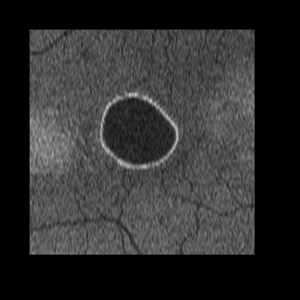

PED_CSCAN

Aug 27 2012 by John S. King, MD

C-Scan

Photographer: Kristin Konecki, OcuSight Eye Care Center, Rochester, NY

Imaging device: Cirrus

Condition/keywords: idiopathic serous detachment of the retinal pigment epithelium